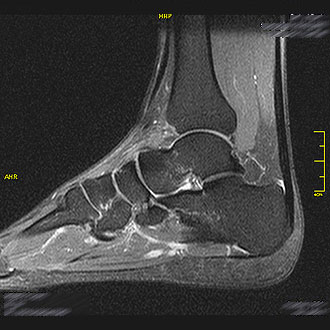

Die MRT des Sprunggelenks wird bei Traumafolgen (Frakturen), Arthrose oder Achillessehnenrupturen durchgeführt.

Auch Streck- und Beugesehnenentzündungen lassen sich detailliert darstellen.

Im Kernspin Zentrum Köln ermöglicht die Untersuchung eine exakte Analyse sowohl des oberen als auch des unteren Sprunggelenks – wichtig für Sportverletzungen und chronische Beschwerden.